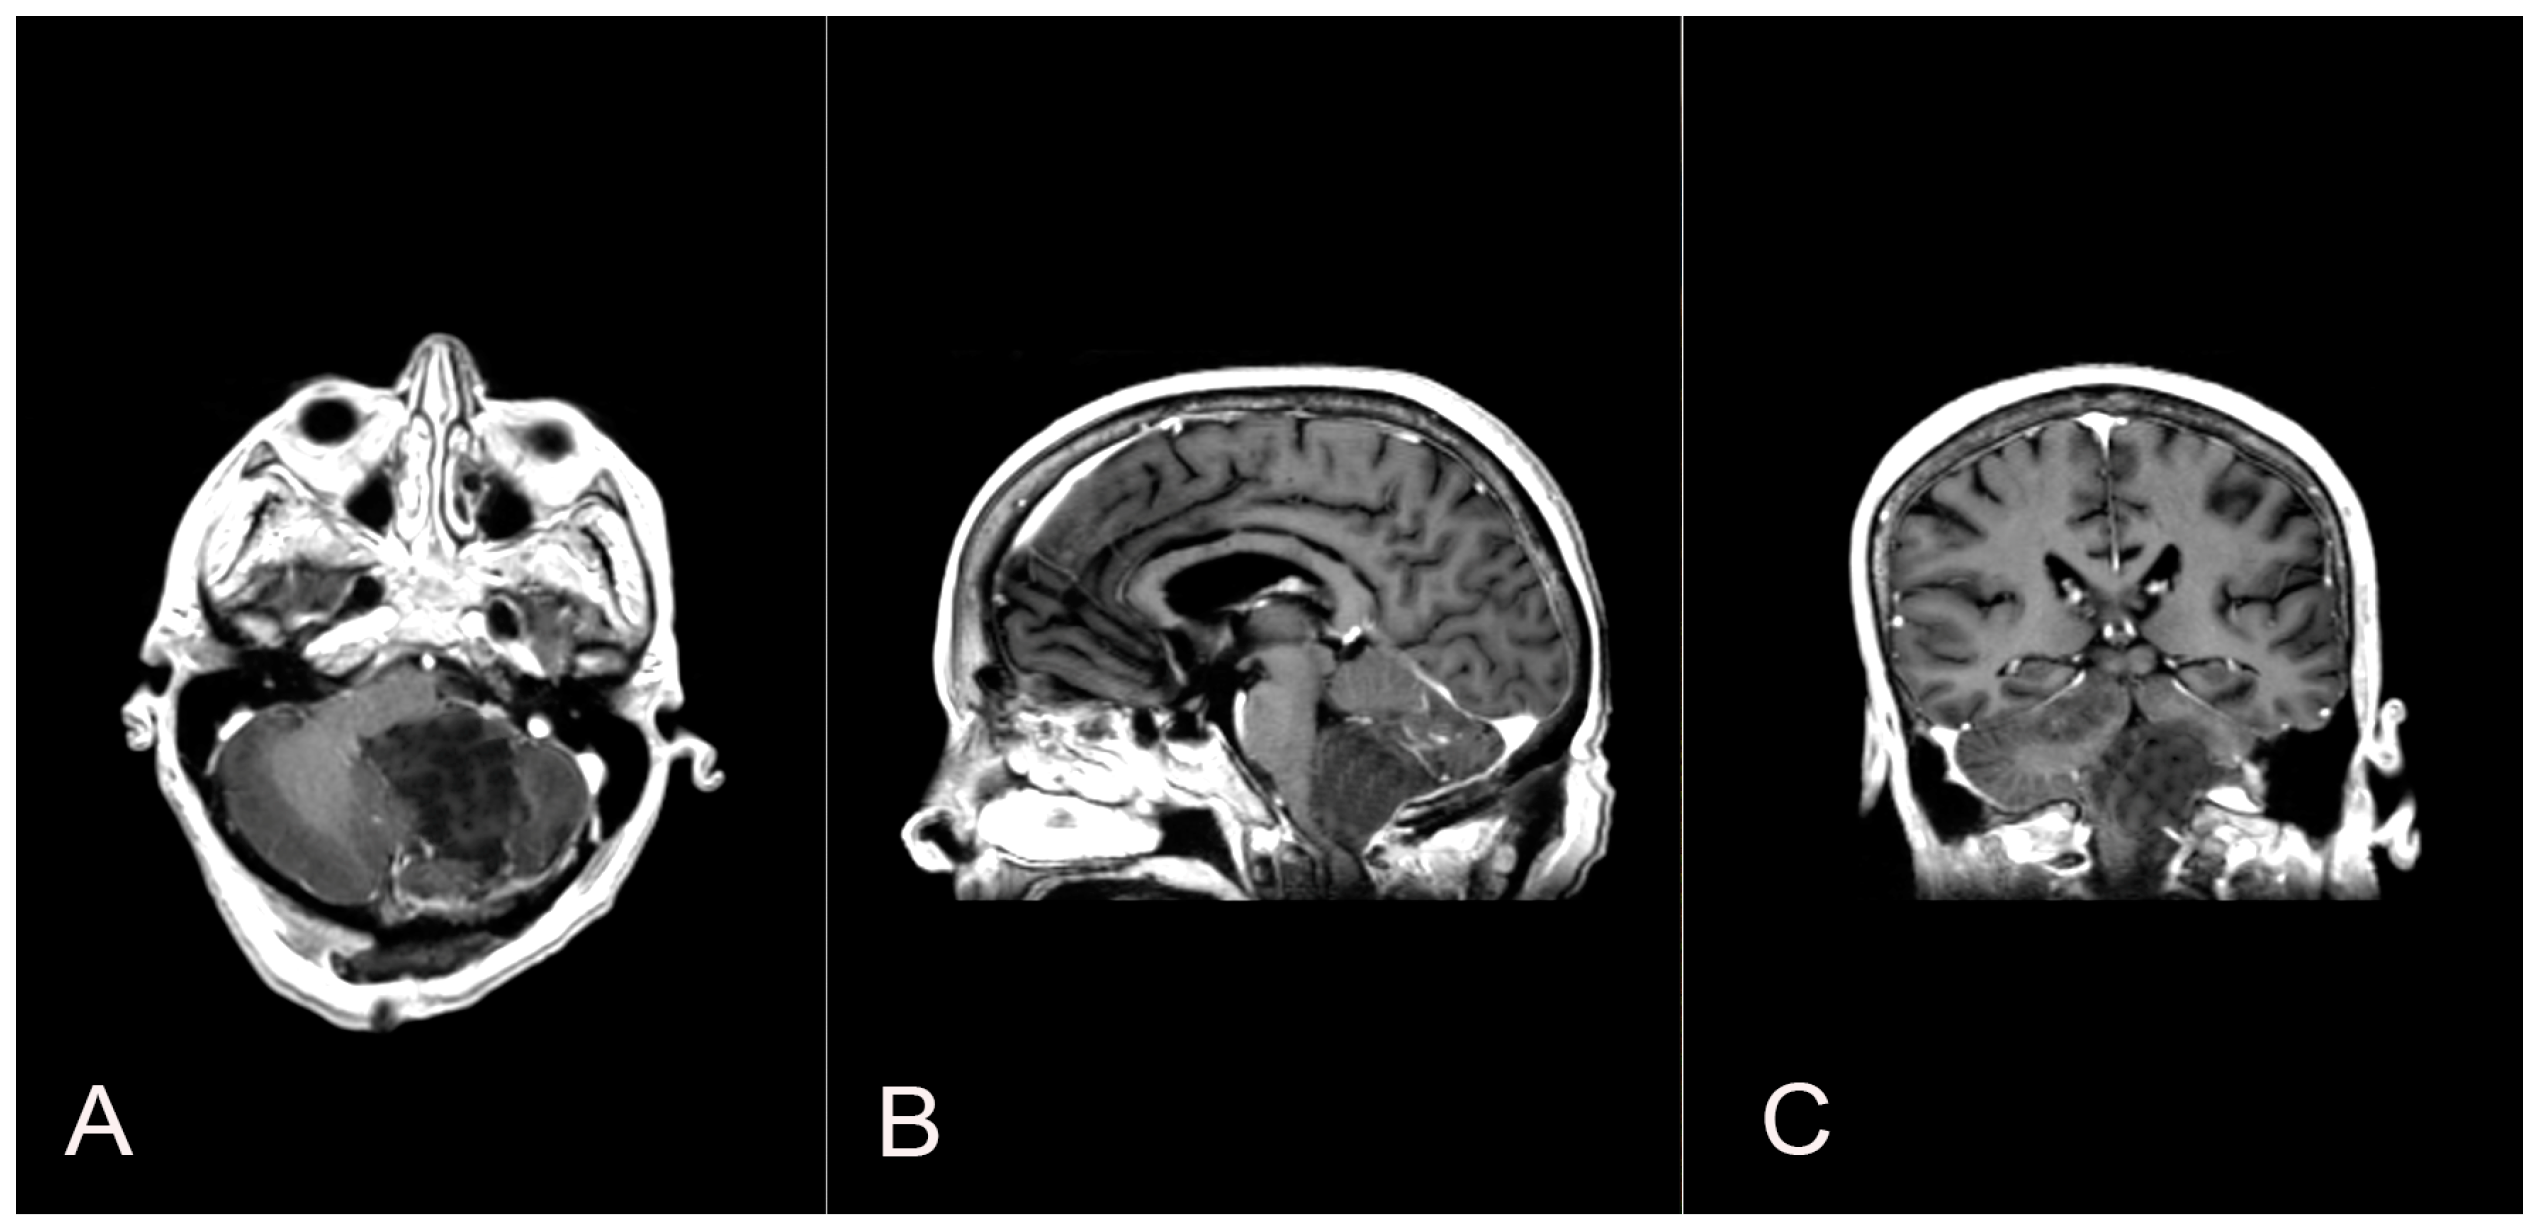

Two years later, a recurrence in the left cerebellar area with inhomogeneous enhancement of 4.5 mm × 15 mm was documented (Figure 4). The patient developed gait disturbances, bilateral left heartbeat nystagmus, a positive Romberg sign, finger-to-nose dysmetria on the left and heel-to-knee dysmetria on the right. A second surgery was performed through a telo-velar approach. The lesion appeared to be a calcified mass tenaciously attached to contiguous structures. A portion of the tumor was found to be tightly adherent to the left lateral recess, which was left in situ after a positive irritative response during the neurostimulation of the XII cranial nerve. The procedure was entirely supported by intraoperative neurophysiological monitoring. The subsequent postoperative course was uneventful (Figure 5). Histopathological examination was consistent with the previous findings of low-grade glioneuronal neoplasia. This entity, not specifically categorized in the current classification (WHO 2021), could be referred to as an infratentorial glioneuronal tumor (Figure 6).

Figure 4.

A follow-up contrast-enhanced brain MRI two years after the first surgical intervention shows the presence of a recurrence in the left cerebellar area with inhomogeneous enhancement (A,B).